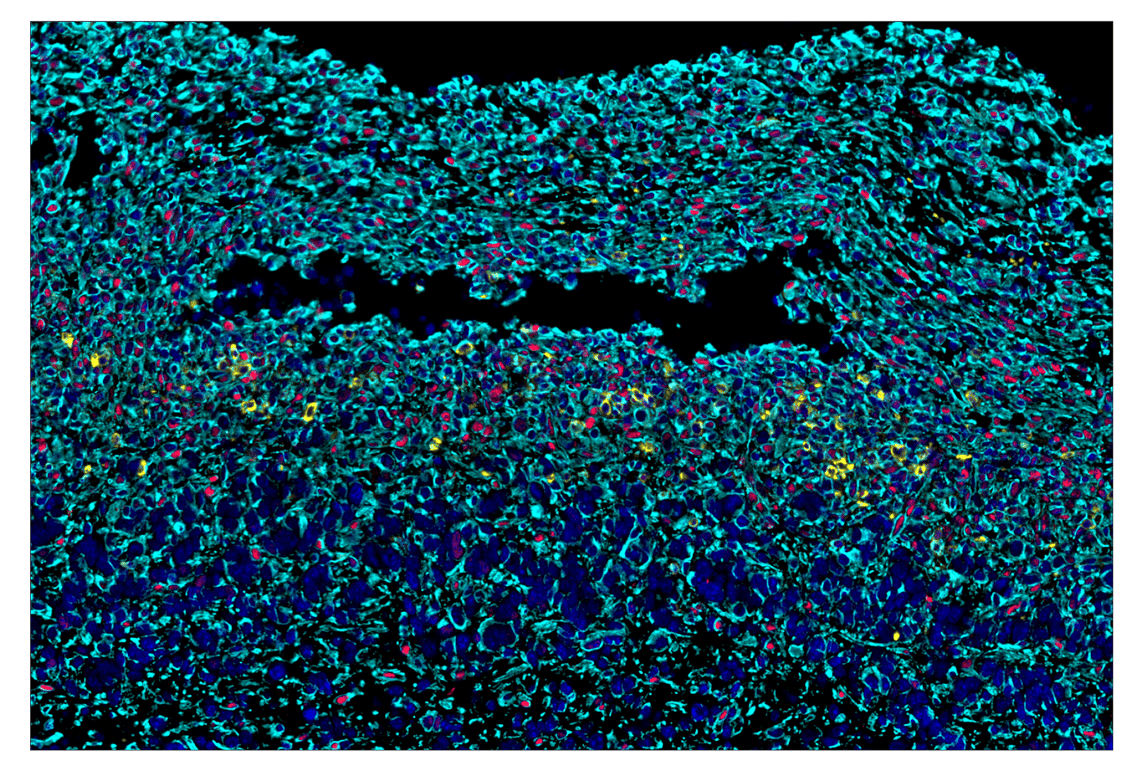

SignalStar™ multiplex immunohistochemical analysis of paraffin-embedded human gastric adenocarcinoma using ICOS (D1K2T™) & CO-0027-488 SignalStar™ Oligo-Antibody Pair #92797 (green), CD45 (Intracellular Domain) (D9M8I) & CO-0013-594 SignalStar™ Oligo-Antibody Pair #15734 (yellow), Phospho-SLP-76 (Ser376) (E3G9U) & CO-0018-647 SignalStar™ Oligo-Antibody Pair #83271 (red), CD16 (D1N9L) & CO-0031-750 SignalStar™ Oligo-Antibody Pair #48056 (cyan), and ProLong Gold Antifade Reagent with DAPI #8961 (blue). All fluorophores have been assigned a pseudocolor, as indicated. Staining was performed on the BOND RX autostainer by Leica Biosystems.

Immunohistochemistry Image 1: Phospho-SLP-76 (Ser376) (E3G9U) & CO-0018-750 SignalStar<sup>™</sup> Oligo-Antibody Pair